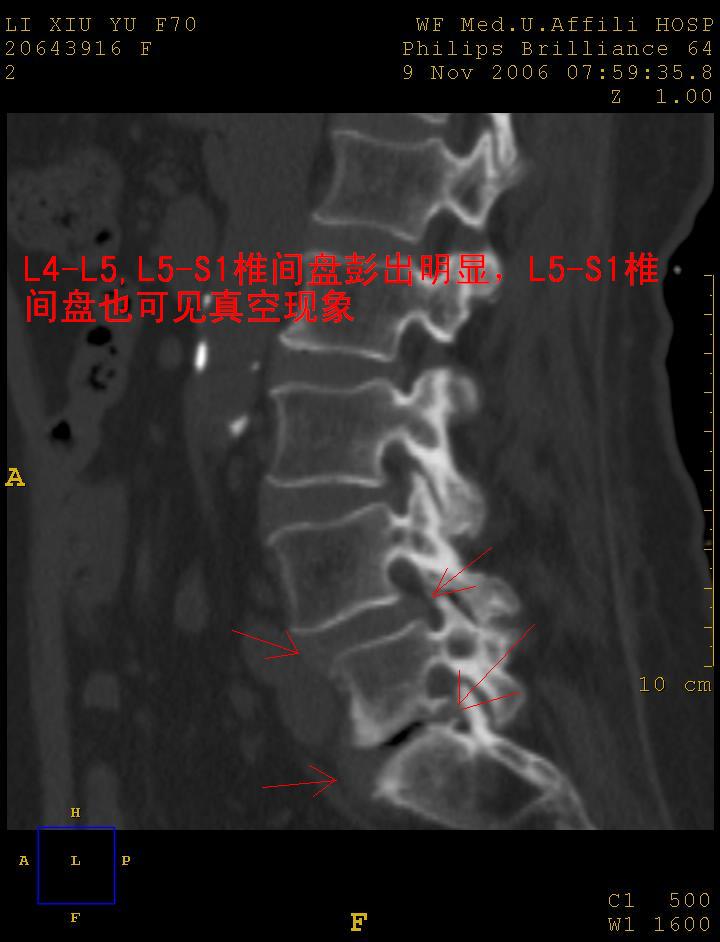

女,70岁,腰痛

1 腰4椎弓崩裂,腰4椎体向前ι度滑脱并椎小关节交锁,腰4/5小关节明显增生硬化,间隙内可见真空征。

2 腰椎间盘不同程度膨出,腰4/5、腰5/骶1椎间盘突出,腰4/5椎间隙变窄,腰5/骶1间盘变性(间隙内可见真空征)。

3 诸椎体缘不同程度骨质增生,腰5、骶1后骨刺明显,腰5椎体后上缘可能有软骨结节(由于没有平扫,不易确定)。

诊断:腰椎退行性骨关节病。